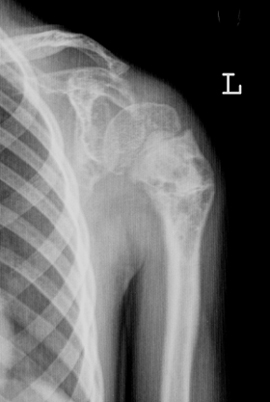

标题: 原创有病理结果,肩关节骨肿瘤。

男,6y,肩关节疼痛2年。

shi he肿瘤

血管瘤

骨纤